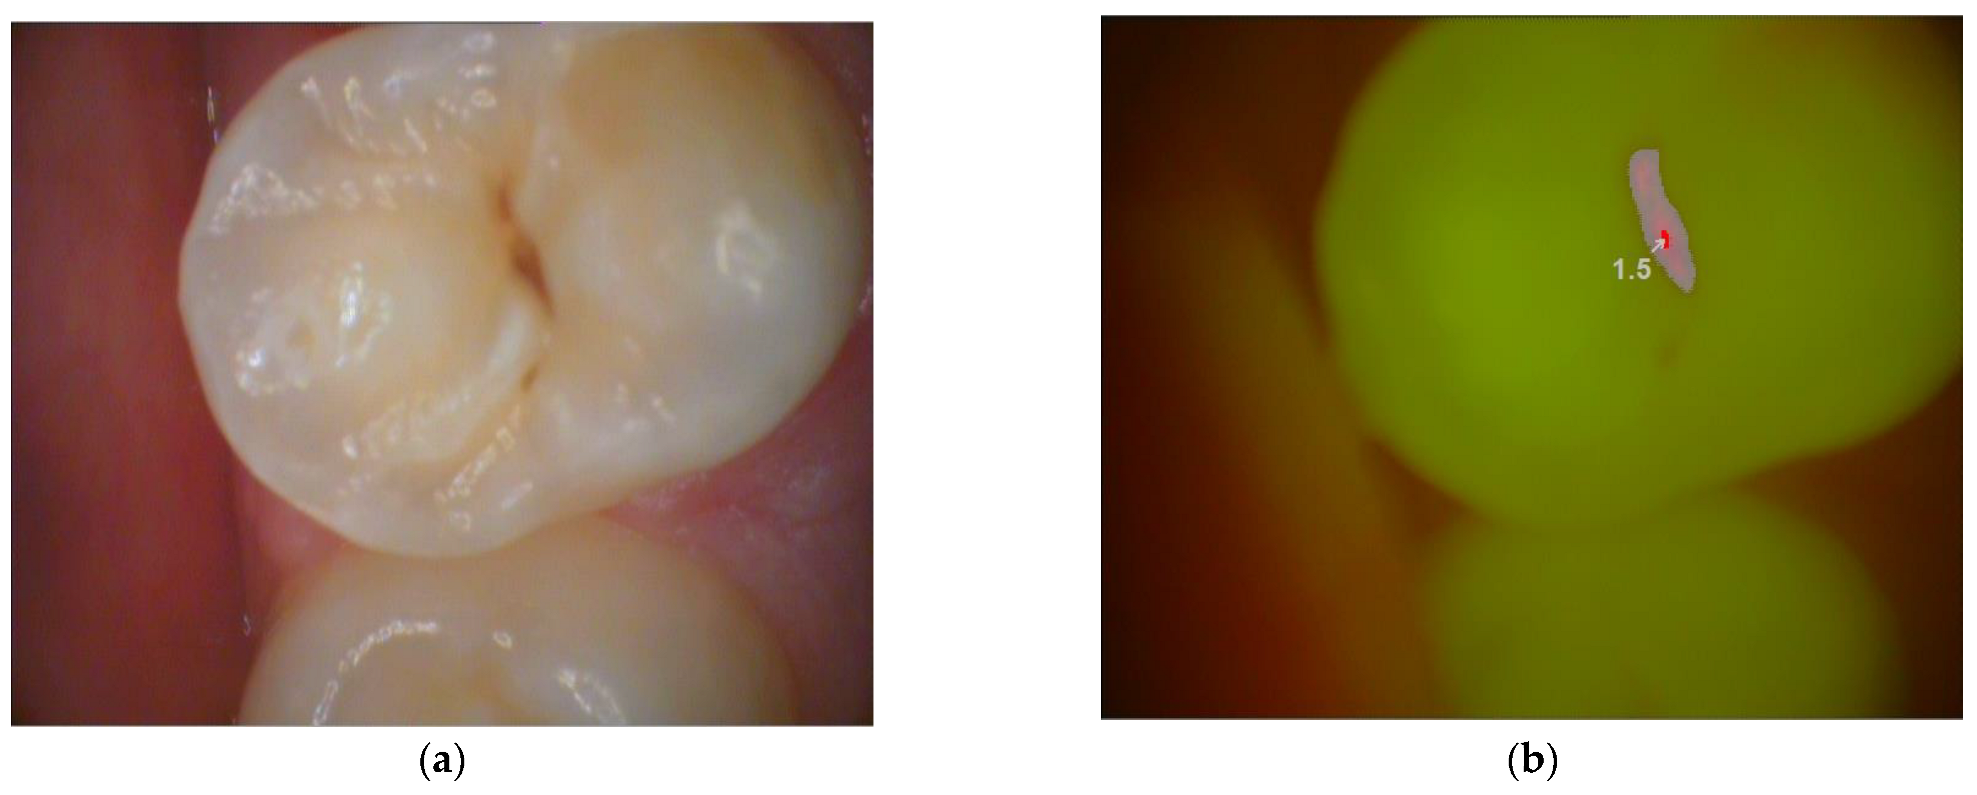

Figure 3.

Picture of a permanent premolar taken by light-induced fluorescence device. (a) With magnifying lens, (b) using the fluorescent mode of VistaCam iX. (Dürr Dental, Germany).